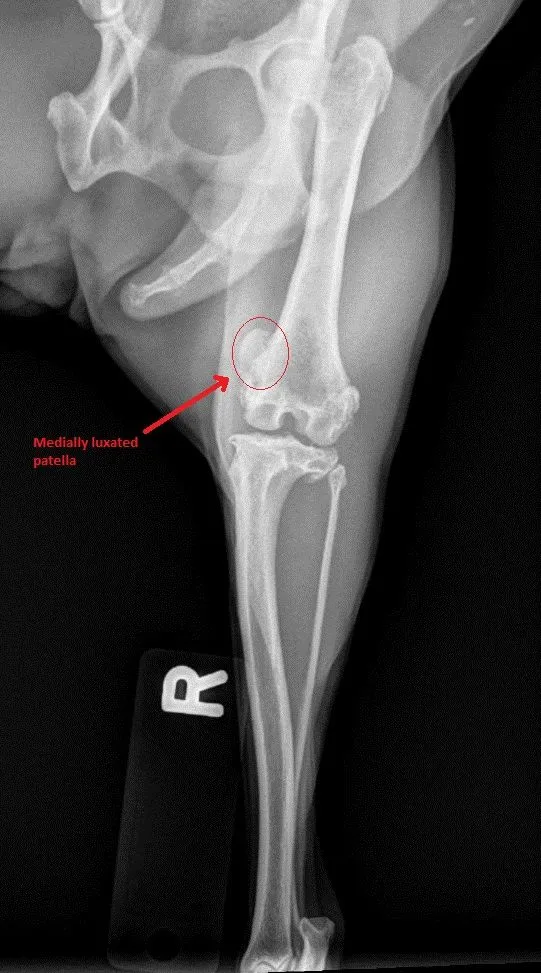

Patellar Luxation aka Luxating Knee caps most commonly seen in Toy breeds where knee cap is most commonly luxation to medial (inner side of knee joint) side resulting bowing of rear limb/limbs ,unstable knee prone to ACL inury and Chronic Arthritis. Surgical correction usually help to stabilize knee, reduce pain and slow down arthritis progression.